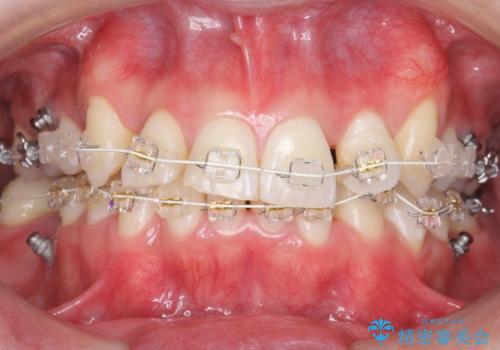

八重歯の矯正+歯のないところにインプラント

- 八重歯を主訴に来院。

下の歯がないところに、奥歯が倒れこんでいたため、矯正治療で倒れこんだ歯を起こして、インプラントを植立しました。

上の前歯が下の前歯に大きく重なっており、過蓋咬合を呈していました。

患者様が事情により、取り外し式のゴムやバイトプレートなどを使用できず、使える手段に限りがある中での治療でしたが、無事に治療を終えることができました。

上顎の小臼歯2本、下顎の親知らずを抜歯しています。

八重歯の移動のため、矯正用ミニスクリューを使用しています。